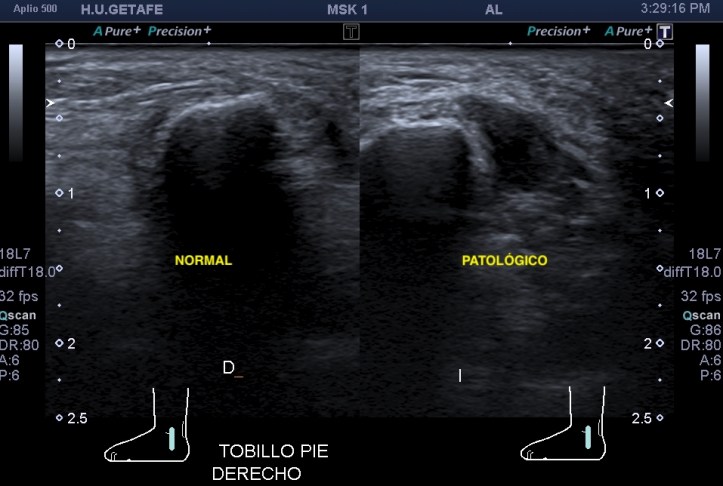

Evidentemente es una imagen patológica comparada con una normal contralateral, la anatomía de la región patológica está cambiada, el hueso está irregular, comparativamente con la zona normal. Esos cambios en el hueso se visualizan en la espina iliaca inferior, donde inserta el tendón del recto anterior, pero este tendón no solo inserta fibras ahí, sino que algunas de ellas insertan justo en la región superior del acetábulo,imagen 3, es decir, justo antes de la inserción en la espina iliaca anteroinferior, algunas se bifurcan hacia profundo, buscando el acetábulo.

La imagen 2 es centrándonos en la zona de patología, aún más espectacular. Se observa la deformación global del hueso en esa zona marcado con flecha amarilla plana.